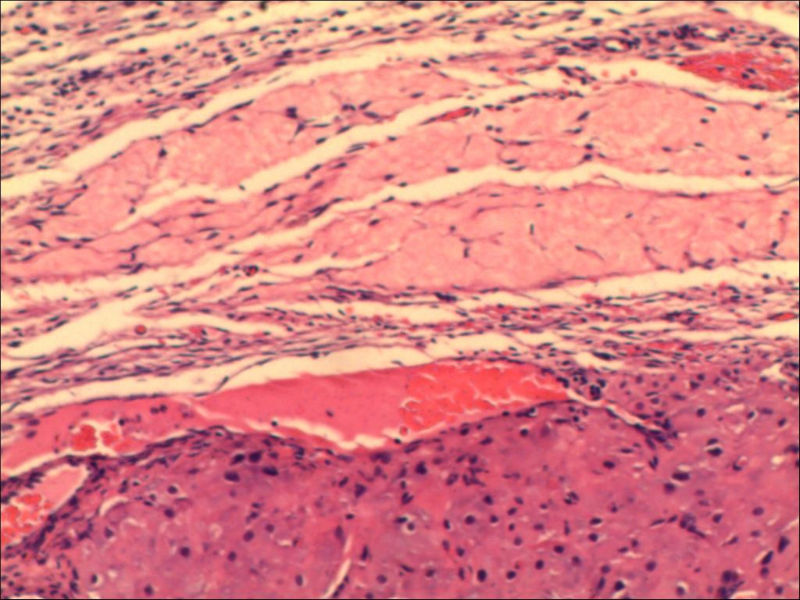

女,27岁,送检右侧卵巢肿物(另外还送检左侧卵巢肿物,大体及镜下显示为畸胎瘤),卵圆形,大小2×1×1cm,似有包膜。卵巢肿物图1

卵巢畸胎瘤中正常卵巢的黄体组织,铺砖样排列,胞浆宽大,较典型。

不好意思,可能是我没说清楚,患者对侧卵巢是畸胎瘤,不是同一侧的,我初步考虑门细胞瘤,图21,22,24,25,26中央的一些细胞是不是很像门细胞

谢谢大家的回答和解疑,忘记一个重要的病史,就是该女性为产妇。但是妊娠黄体瘤与类固醇细胞瘤怎么鉴别呢

那应该是妊娠黄体/黄体瘤,类固醇细胞瘤有嗜酸细胞和组织细胞样细胞两种,此例显然不是。